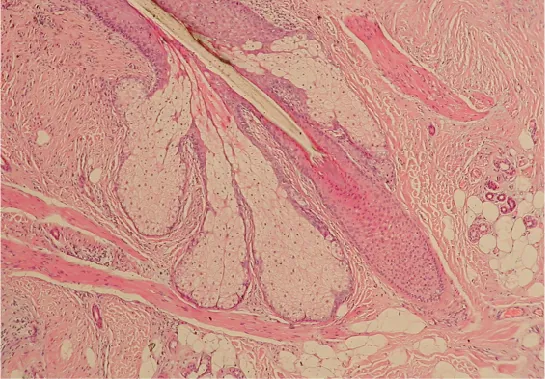

This micrograph is of the base of a hair follicle. The protruding hair is largely transparent, with only its dark outline visible. The inner root sheath is visible surrounding the very bottom of the hair as a circle of cells with dark-staining nuclei. The inner sheath extends up the hair shaft. The outer root sheath is much thicker than the inner root sheath, consisting of a large oval of lighter staining cells. The oval surrounds the bottom of the hair and extends into the hypodermis.

Figure 5.12 Hair Follicle The slide shows a cross-section of a hair follicle. Basal cells of the hair matrix in the center differentiate into cells of the inner root sheath. Basal cells at the base of the hair root form the outer root sheath. LM × 4. (credit: modification of work by “kilbad”/Wikimedia Commons)